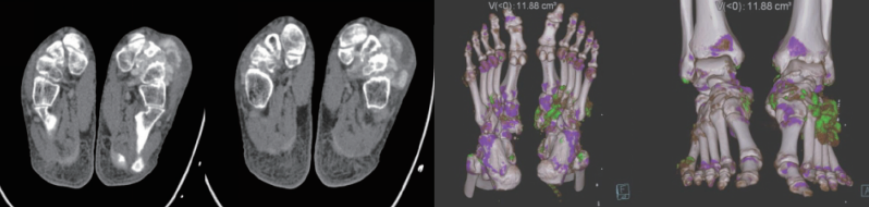

案例圖

痛風石檢測